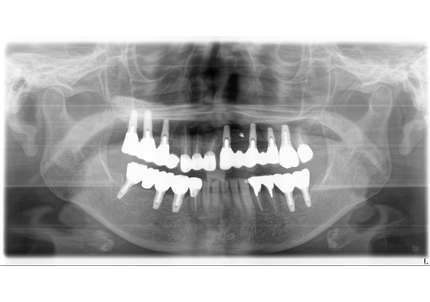

24.パノラマレントゲン

↑2006年4月24日(初診時)

↑2024年6月26日